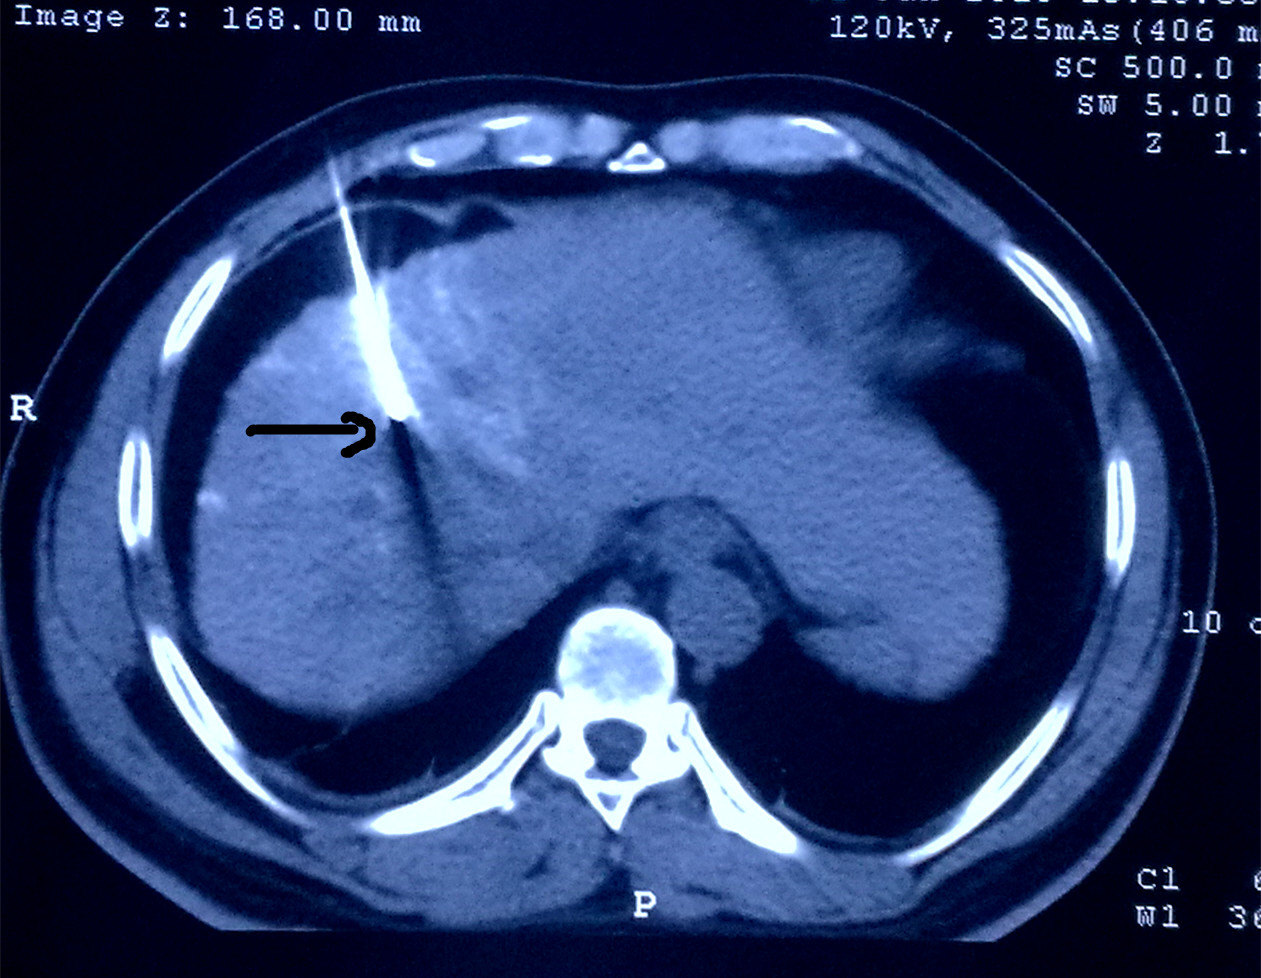

术前必须搞明白,立马做DSA,果真发现另外两个微小病灶,一个在8段,一个在5段,随即做了TACE,将三个病灶全部栓塞。一周后在CT引导下我用射频将三个病灶全部毁损,效果很不错。